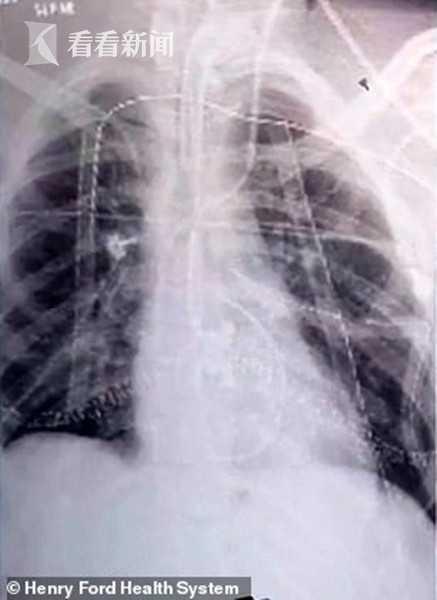

美国一名17岁少年因吸食电子烟导致双肺坏死 , 命悬一线 。 近日医生为其进行了双肺移植手术 , 称血淋淋的教训足以警惕人们"吸电子烟的下场"!

据英国《每日邮报》11月12日报道 , 这名17岁的男性患者姓名未予公开 。 今年9月5日 , 他首次被密歇根州一家医院收治 , 症状疑似肺炎 , 但病情迅速恶化 , 10月3日被转移至密歇根州儿童医院抢救前 , 已经做了插管 。

CT结果显示 , 少年的双肺已变成疤痕组织 , 据此判断他离死亡只剩下几天时间 。 10月15日 , 医疗小组耗时6小时为他做了双肺移植手术 , 由此少年成为美国第一个接受双肺移植的肺气肿患者 。 虽然性命保全 , 但医生称他还有很长的康复之路要走 。